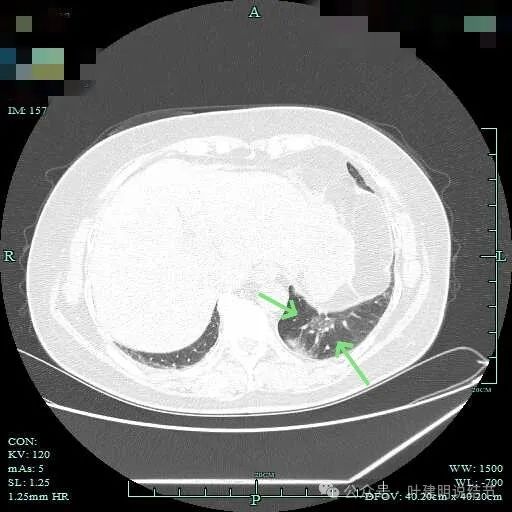

病灶轮廓欠清,较为散在,缺乏聚拢性,似乎有些像斑点状。

有少许磨玻璃成分出现,较前面层面整体轮廓显得清楚点。

到这层面,聚拢性较前明显,密度显杂乱。

磨玻璃成分更明显,实性成分也明显,实性部分收缩力不强,表面不平整,感觉边缘毛糙。

表面浅分叶,磨玻璃成分明显,实性部分密度较高。

表面不平,磨玻璃部分的轮廓与边界清,实性部分占比不小,缺乏收缩力,像是腺泡型。

实性成分占比较高,边上有明显磨玻璃成分,说明含贴亚型。

灶内有小空泡征,磨玻璃部分轮廓与边界清,实性部分虽明显但毛刺征或收缩力等均不明显。

磨玻璃成分以及灶内空泡征。

灶内细支气管扩张明显,实性成分缺乏收缩力,考虑腺泡亚型。

磨玻璃成分也很明显,考虑含贴壁亚型。

上图大部分是磨玻璃成分,边缘的毛刺征,表面有浅分叶。

上图层面已经基本上磨玻璃密度,轮廓清,灶内有囊腔样灶,表面不平。

边缘略显糊,与膈肌贴着。

远侧端有阻塞性炎症的表现,病灶在些层也是磨玻璃密度。

边缘区域略显轮廓不清。